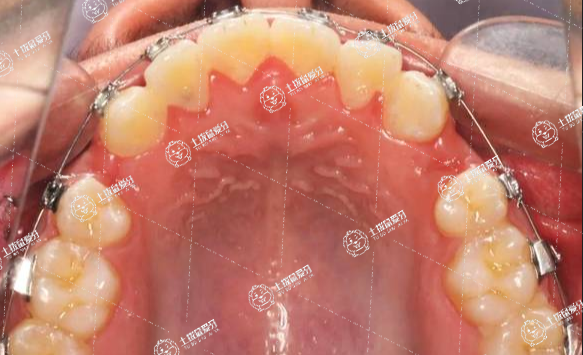

擴弓增大空間

正常的牙弓呈現(xiàn)流暢的卵圓形,如果發(fā)育過程中因為各種原因?qū)е卵拦M窄,造成牙列擁擠,正畸醫(yī)生可以通過擴大牙弓的方式,將牙弓調(diào)整到正常寬度,增加空間,讓擁擠的牙列可以舒展排開,達到排齊的目的。這個方法針對性強,對于牙弓發(fā)育正常的患者來說,擴弓時間較長,擴大的空間也有限,并不能很好地解決擁擠問題,不是所有人都適用。